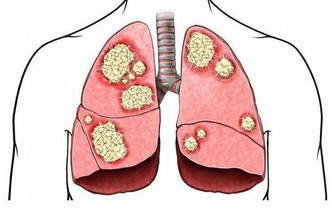

酒精容易引起酒精性肝炎、肝纖維化、肝硬化等情形,

而肝癌也是我國常見的惡性腫瘤之一,常見於中年男性。

因其惡性度高、病情進展快,病人早期一般沒有什麼不適,

一旦出現症狀就診,往往已屬中晚期。

長期酗酒,體內的乙醛就會蓄積,最終可能導致肝癌發生。